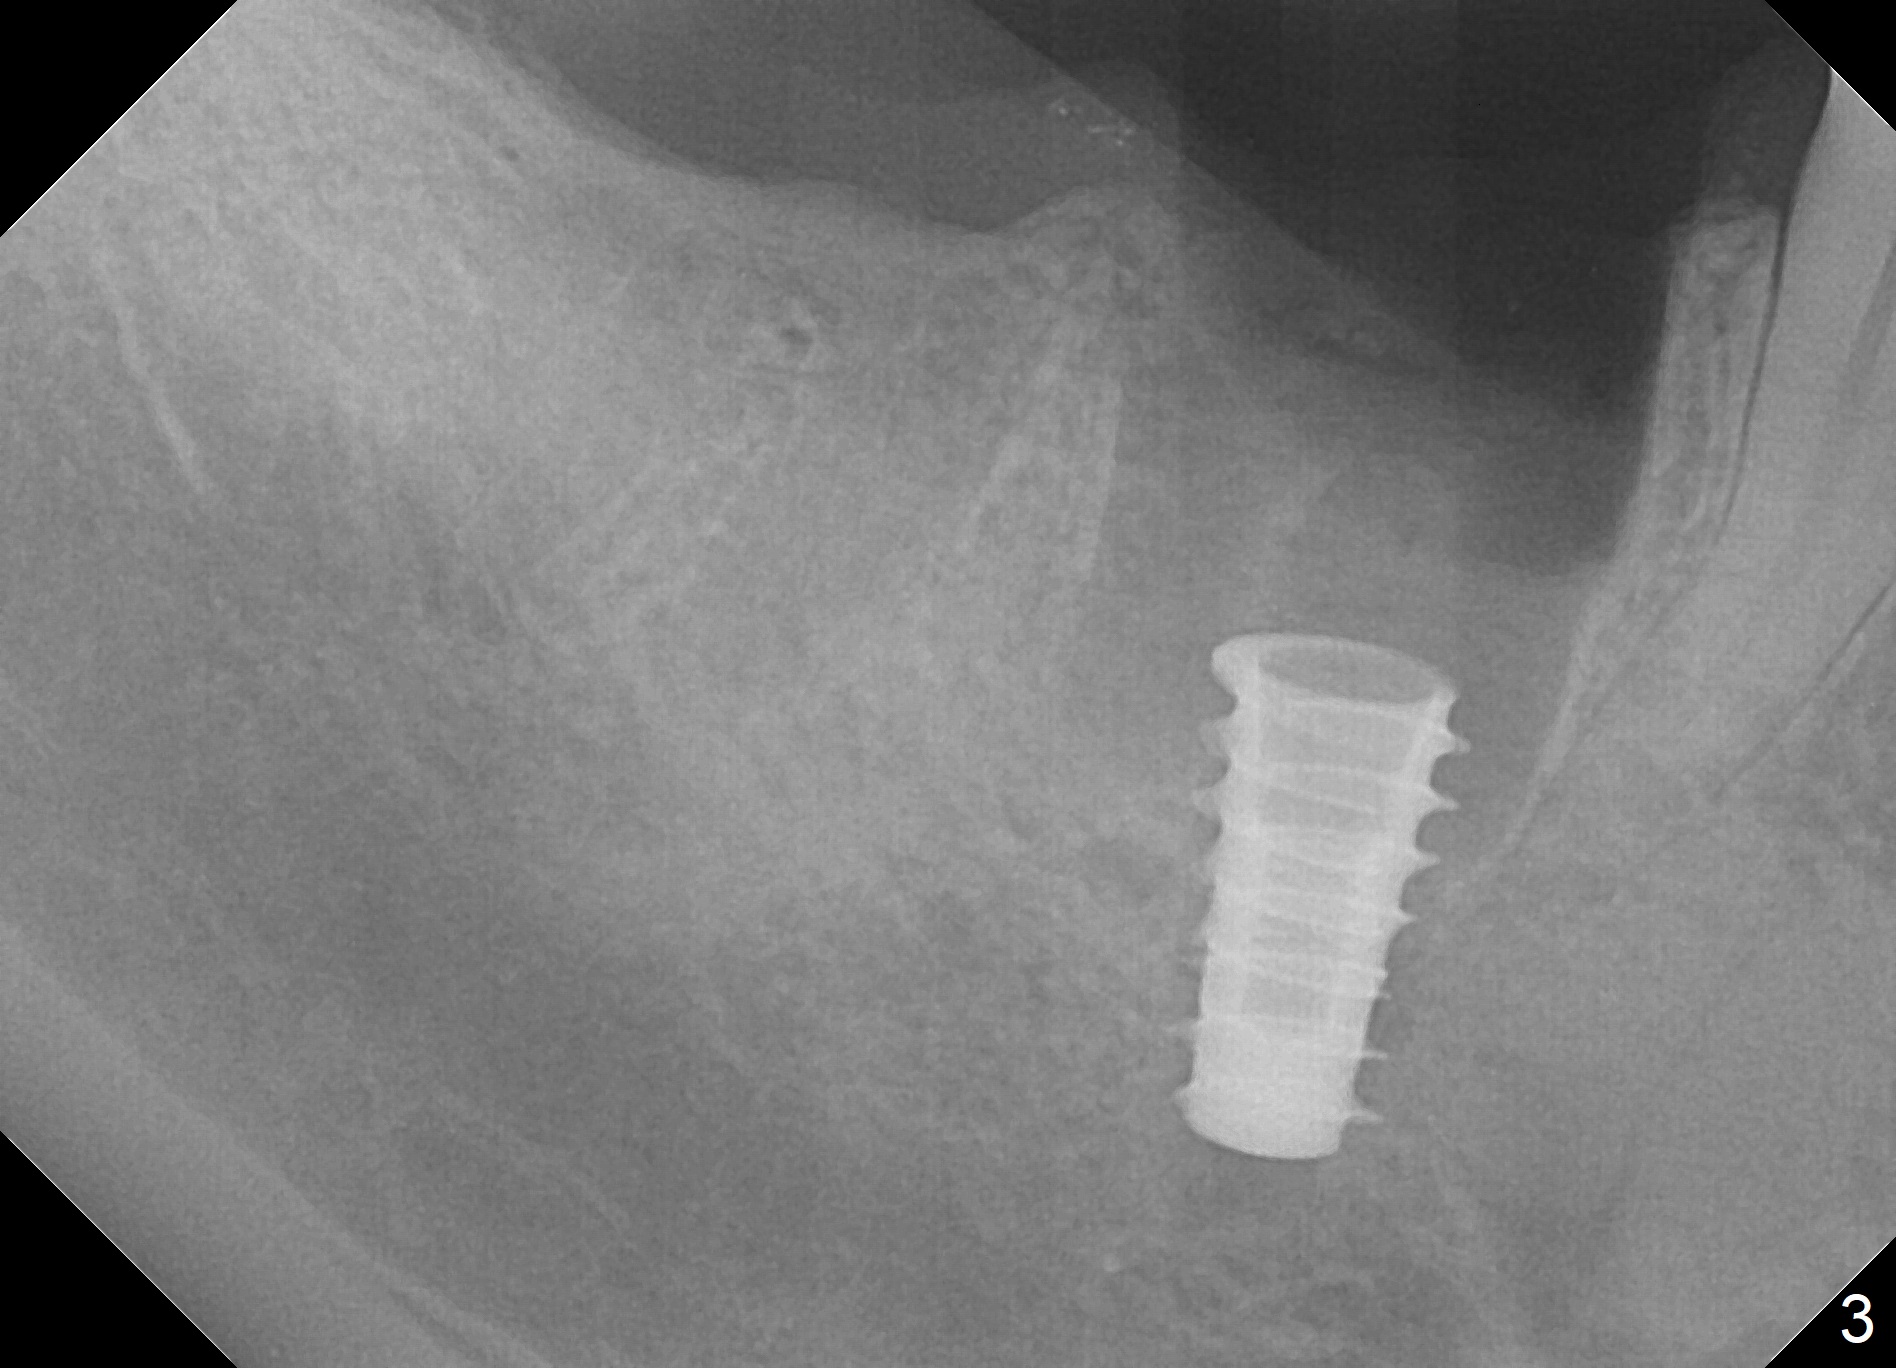

Extraction is difficult due to hard bone and brittle, curved roots of the tooth #30; initial depth in the septum is 14 mm (gingival level, Fig.1). Then the depth increases to 17 mm; with sequential osteotomy using 2.8 mm to 4.8 mm Magic Drills (MD), a 5x9 mm dummy implant is placed incompletely due to hard bone (Fig.2). After use of 5.3 mm MD for ~ 15 mm, the dummy implant is placed to the depth (Fig.3). The definitive IBS implant (5x13 mm) is placed with 50 Ncm; a 6.5x5.7(4) mm abutment is placed with allograft filling the gap (* and arrow).